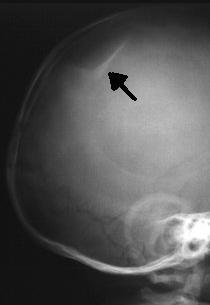

Diffuse axonal injury: illustration. - Skull Fractures (Depressed, Basilar, Linear, Comminuted, Compound), Otorrhea, Rhinorrhea, Ottorhagia,

Skull Fracture.